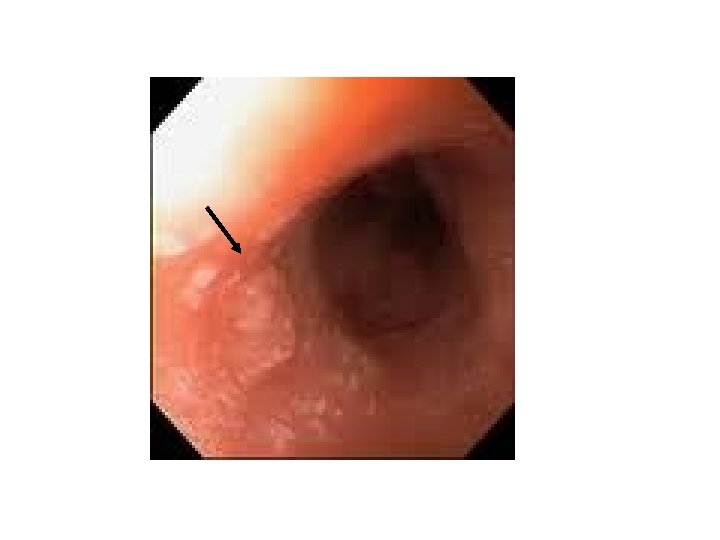

ESÓFAGO: CARCINOMA ESCAMOSO • ANATOMÍA PATOLÓGICA – Afecta a 2/3 superiores del esófago – Existe una lesión epitelial precedente: displasia epitelial • • • Bajo grado Moderado Alto grado Carcinoma in situ Carcinoma infiltrante evolución temporal (años) – ESTUDIO MACROSCÓPICO • Las lesiones de displasia/carcinoma in situ suelen ser lesiones algo sobreelevadas, con cambios en la coloración y aspecto del esófago • Carcinoma infiltrante: – Masa polipoide exofítica (60%) – Úlceras (20%) – Lesión difusa que engrosa la pared (15%)

c. Escamoso exofítico y polipoide

c. Escamoso estenosante

c. Escamoso endofítico, ulcerado